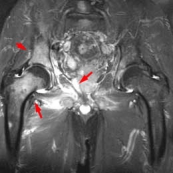

- atteinte du bassin, du rachis